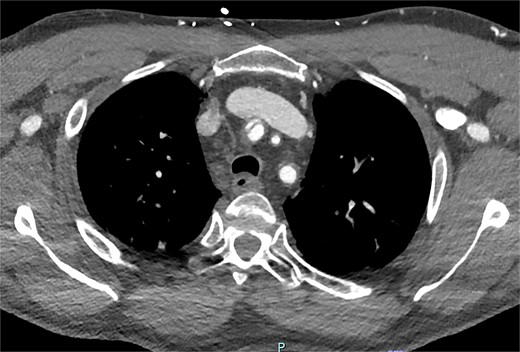

On arrive to the emergency department, the patient was found to be hypertensive with a blood pressure of 220/120 mmHg. Physical examination of the patient revealed no significant clinical findings. Serial troponins with corresponding ECG’s were undertaken which demonstrated no new evidence of myocardial ischaemia. Based upon the patient’s symptomatology, he underwent a CT aortogram which demonstrated a dissection arising from the proximal brachiocephalic artery. No dissection was noted in the ascending aorta, and there was no evidence of the brachiocephalic artery dissection extending into the subclavian or carotid arteries (Figs 1–3).

Axial slice from CT aortogram in greater detail of the dissection flap.